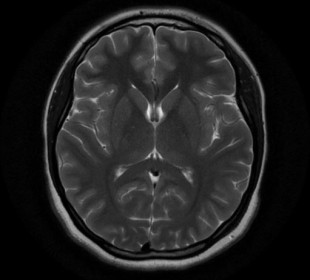

Российские ученые разрабатывают приложение, способное выявить рак мозга на ранней стадии

Специалисты из МГМУ имени Сеченова создали приложение, которое способно выявлять на МРТ-снимках опухоли головного мозга. Кроме того, искусственный интеллект способен определить локализацию и тип новообразования. Одна из целей амбициозного проекта – снизить нагрузку на врачей-рентгенологов и повысить точность и эффективность ранней диагностики. На данный момент точность определения – 97,1%.Приложение имеет открытый код, благодаря чему возможно совместна работа различных специалистов.